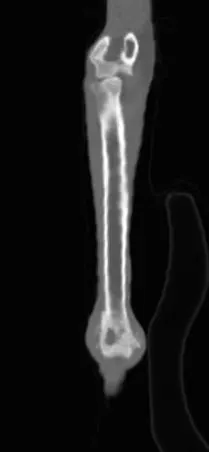

Osteosarcoma (OSA) is the most common primary bone tumor in dogs.5 Unfortunately, most cases are not cured with surgery because of the high risk for metastatic disease.5 Patients should be staged for gross metastasis to lung or another bone before surgery (Figure 2). Staging methods vary depending on clinician preference, but 3-view thoracic radiographs and/or thoracic CT and bone scan are recommended.6 Limb amputation is the most commonly performed surgical treatment; major benefits include removal with wide margins of the tumor, removal of the source of pain, and removal of potential for ongoing metastasis.

(A) Radiograph of a distal radial osteosarcoma. Centered at the distal metaphysis of the radius, there is evidence of permeative and moth-eaten lysis. There is also concurrent ill-defined periosteal proliferation consistent with an aggressive bone lesion. (B) CT scan of distal radial osteosarcoma in the same patient. Coronal view of limb in bone window. There is more evidence of geographic bone lysis and evidence of periosteal proliferation. Consistent with an aggressive bone lesion. (C) Bone scan of the distal radial osteosarcoma in the same patient. Note the increased uptake of radiopharmaceutical in the distal radius of the patient (arrow).

In some cases, another surgical option may be limb salvage, which is most commonly performed in the distal radius and involves the surgical removal of the affected bone. The defect is most commonly bridged using an endoprosthesis (ie, a metal implant with a bone plate extending from the metacarpals to the proximal radius). Although the limb is usually preserved, the rate of complications (eg, infection, local recurrence, implant failure) is extremely high.7 Limb salvage should only be considered when amputation is not an option for medical reasons (eg, a patient with significant concurrent orthopedic or neurological disorders). There are cases in which a client will not accept amputation and limb salvage is considered; client education in these cases is critical.